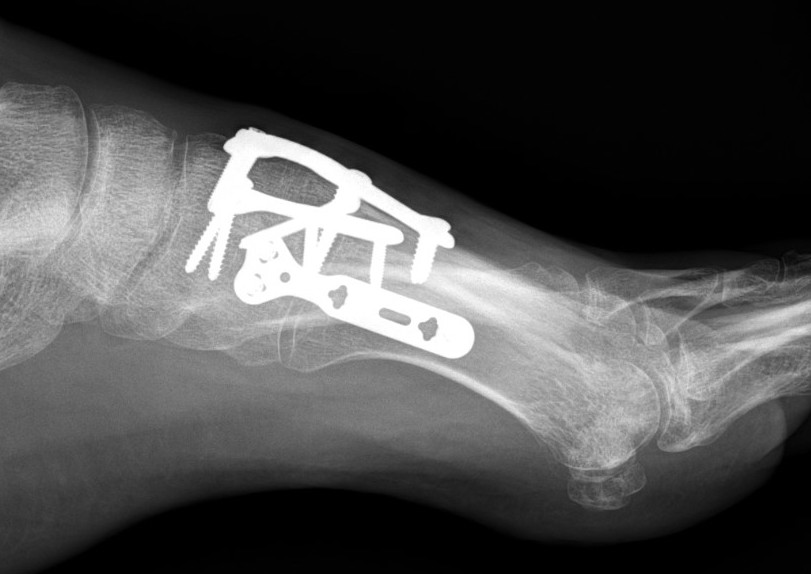

Fusion of 1st TMT, plating of 2nd and 3rd TMT, K wire stabilization of 4th and 5th TMT